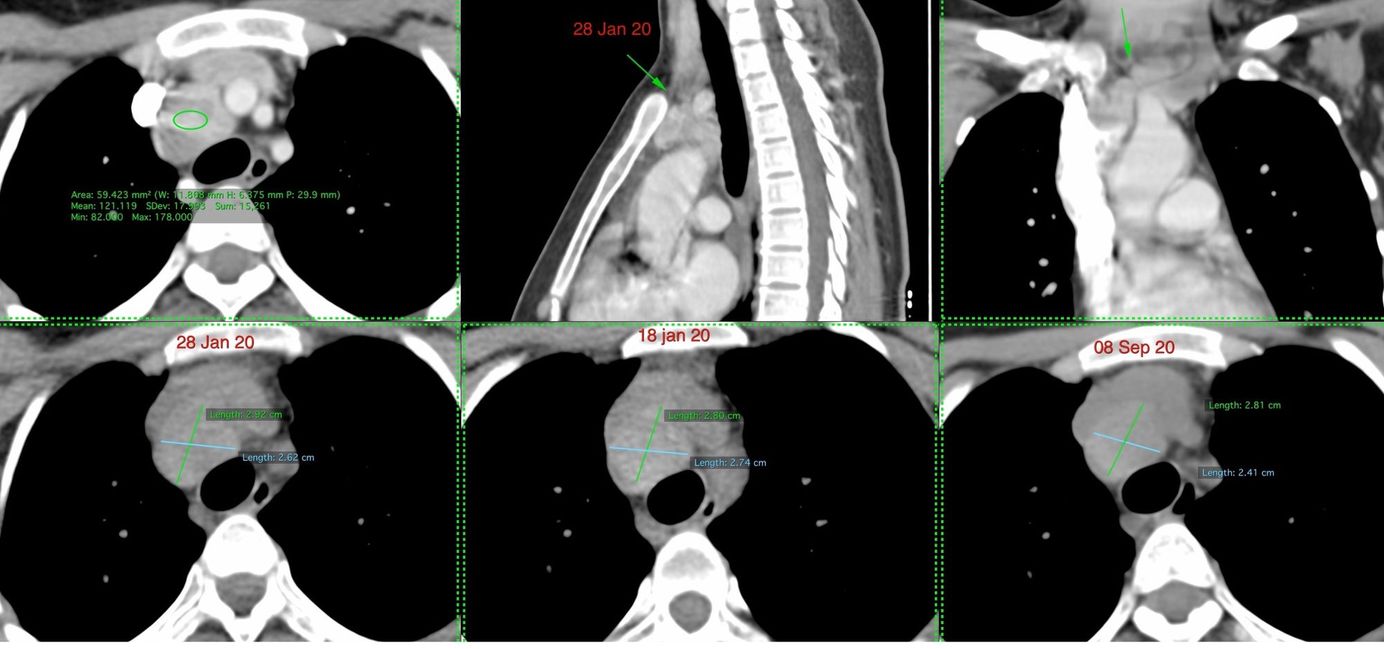

Case 2: Resolution of Covid-19 "fibrosis" at 9 months follow-up Members Public

This case describes significant improvement of the lung lesions at 9 months follow-up as is known from the first SARS experience.